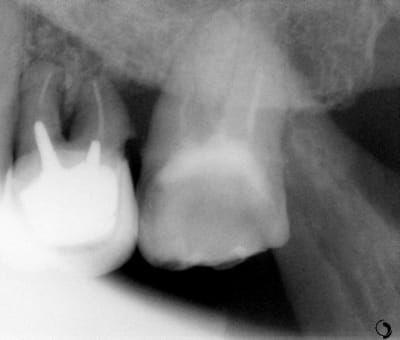

Pour abonder dans le sens qu'il ne faut pas couronner dans tous les cas, voici un cas fait il y a un an.

Les facteurs qui m'ont amené à prendre la décision de faire une endocouronne (proche d'un onlay en vérité) :

- 3 parois solides, la dernière pas trop fine.

- limites toutes supragingivales

- occlusion favorable (pas de photos de l'antagoniste je n'y ai pas pensé)

- patient réceptif

- grande profondeur de la chambre pulpaire (pas très visible sur les photos verticales)

Je n'en fais pas souvent mais quand j'en fait c’est que j'ai confiance. Faire une couronne classique ? Sur ce cas rien que de préparer les limites périphériques et on se retrouve avec une dent à raz la gencive, avec obligation de faire un (ou plusieurs) tenons longs pour une bonne rétention, générateur de fracture radiculaire....

Couronne Emax, collée au Multilink Automix

PS : avant toute remarque, non la patiente ne veut pas que je touche à sa dent de lait résiduelle ;o)